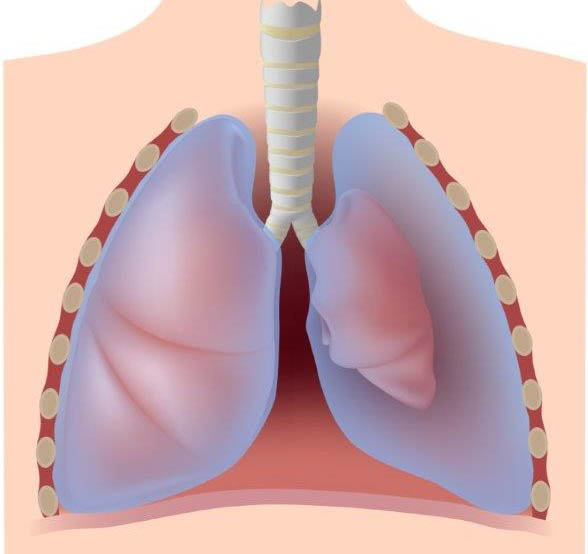

Basicamente, o pneumotórax acontece quando o ar, que deveria estar dentro do seu pulmão, vaza para o espaço pleural. Esse espaço é aquela fina camada que recobre os pulmões e a parede interna do tórax. Pense nele como um vácuo natural que permite que o pulmão se expanda e contraia livremente.

Quando o ar invade esse espaço, ele aumenta a pressão. Essa pressão externa empurra o pulmão, impedindo que ele se encha completamente de ar. O resultado? Um colapso pulmonar, que pode variar de um pequeno encolhimento a um colapso total, dependendo da quantidade de ar que escapou.

É uma condição que pode surgir de repente e sem avisos. E a sensação é de que o próprio corpo está te traindo, dificultando a tarefa mais essencial: respirar.

O pneumotórax traumático, como o nome sugere, vem de um trauma. Pode ser fechado (sem ferida externa visível) ou aberto (com comunicação com o exterior). E o tipo mais perigoso: o pneumotórax hipertensivo. Aqui, o ar entra no espaço pleural, mas não consegue sair, criando uma pressão que comprime não só o pulmão, mas também o coração e os grandes vasos. É uma emergência médica gravíssima que pode levar à morte rapidamente.